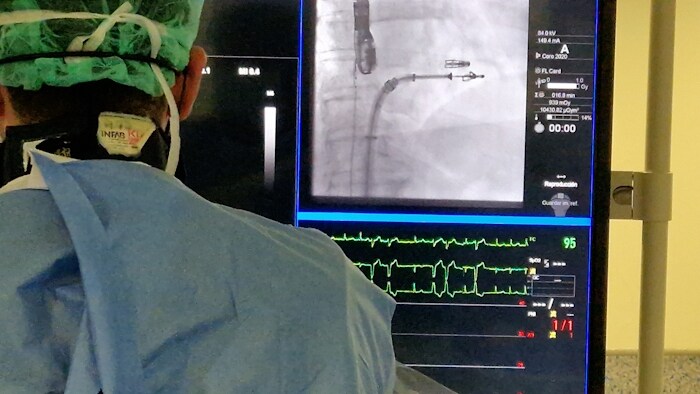

Por ejemplo, los departamentos de cardiología están sometidos a una enorme presión. Los clínicos no sólo tienen que gestionar la prestación de una atención de alta calidad para un volumen creciente de patologías complejas, sino que también deben hacer frente a presiones para mejorar la eficiencia del departamento y mucho más. Desde ayudar a los médicos a adquirir la imagen correcta y analizarla de la forma adecuada, hasta reducir el tiempo de evaluación de las imágenes de RM y TC cardíacas, estamos integrando la IA en toda nuestra cartera para ayudar a los médicos a dar sentido a toda la información de que disponen para que puedan centrarse en lo que importa.